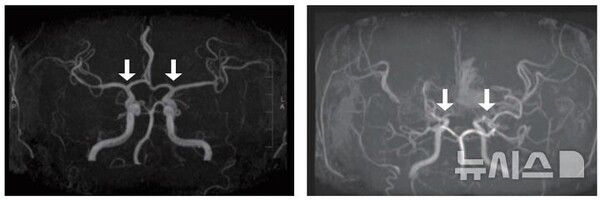

희귀난치성 뇌혈관질환 '소아 모야모야병'의 발생 양상과 치료 및 예후를 전국 단위로 분석한 결과가 나왔다.

모야모야병은 뇌로 혈액을 공급하는 혈관이 원인 없이 점차 좁아지는 만성 진행성 뇌혈관질환이다. 10세 전후 소아와 40세 전후 성인에서 주로 발병하며, 부작용으로는 뇌혈관이 막히거나 파열되는 허혈성·출혈성 뇌졸중이 있다.